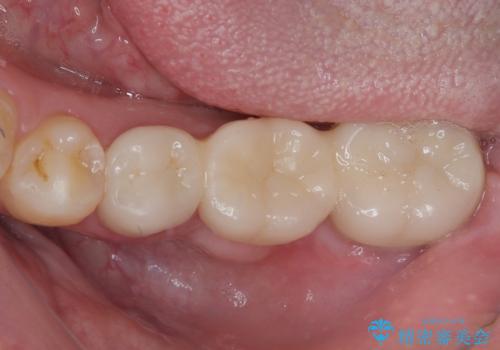

まずは奥歯の痛みを改善し、その後矯正治療を行い、最後にオールセラミックブリッジによる補綴治療を行うこととしました。

むし歯をきっかけに矯正治療を行うこととなりましたが、学生の頃から気になっていた歯列を改善することができ、患者様には大変満足していただけました。